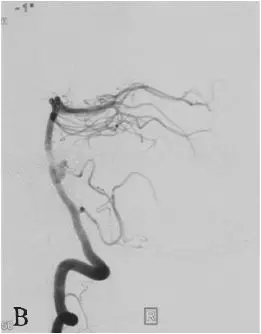

DSA:急诊全脑血管造影提示右侧颈内动脉发出变异的原始三叉动脉,该三叉动脉直接向右侧小脑前下动脉(AICA)供血区域供血,在原始三叉动脉自颈内动脉发出部位可见1枚梭形动脉瘤(图18-1B、C),右侧椎动脉发育较差,仅供血小脑后下动脉(PICA)区域(图18-1D)。右侧小脑前下动脉(AICA)未见显影,可见基底动脉发出的部分回旋支显影(图18-1E)。其余血管造影未见明显异常。

B:右侧颈内动脉造影;

C:右侧颈内动脉造影三维重建;